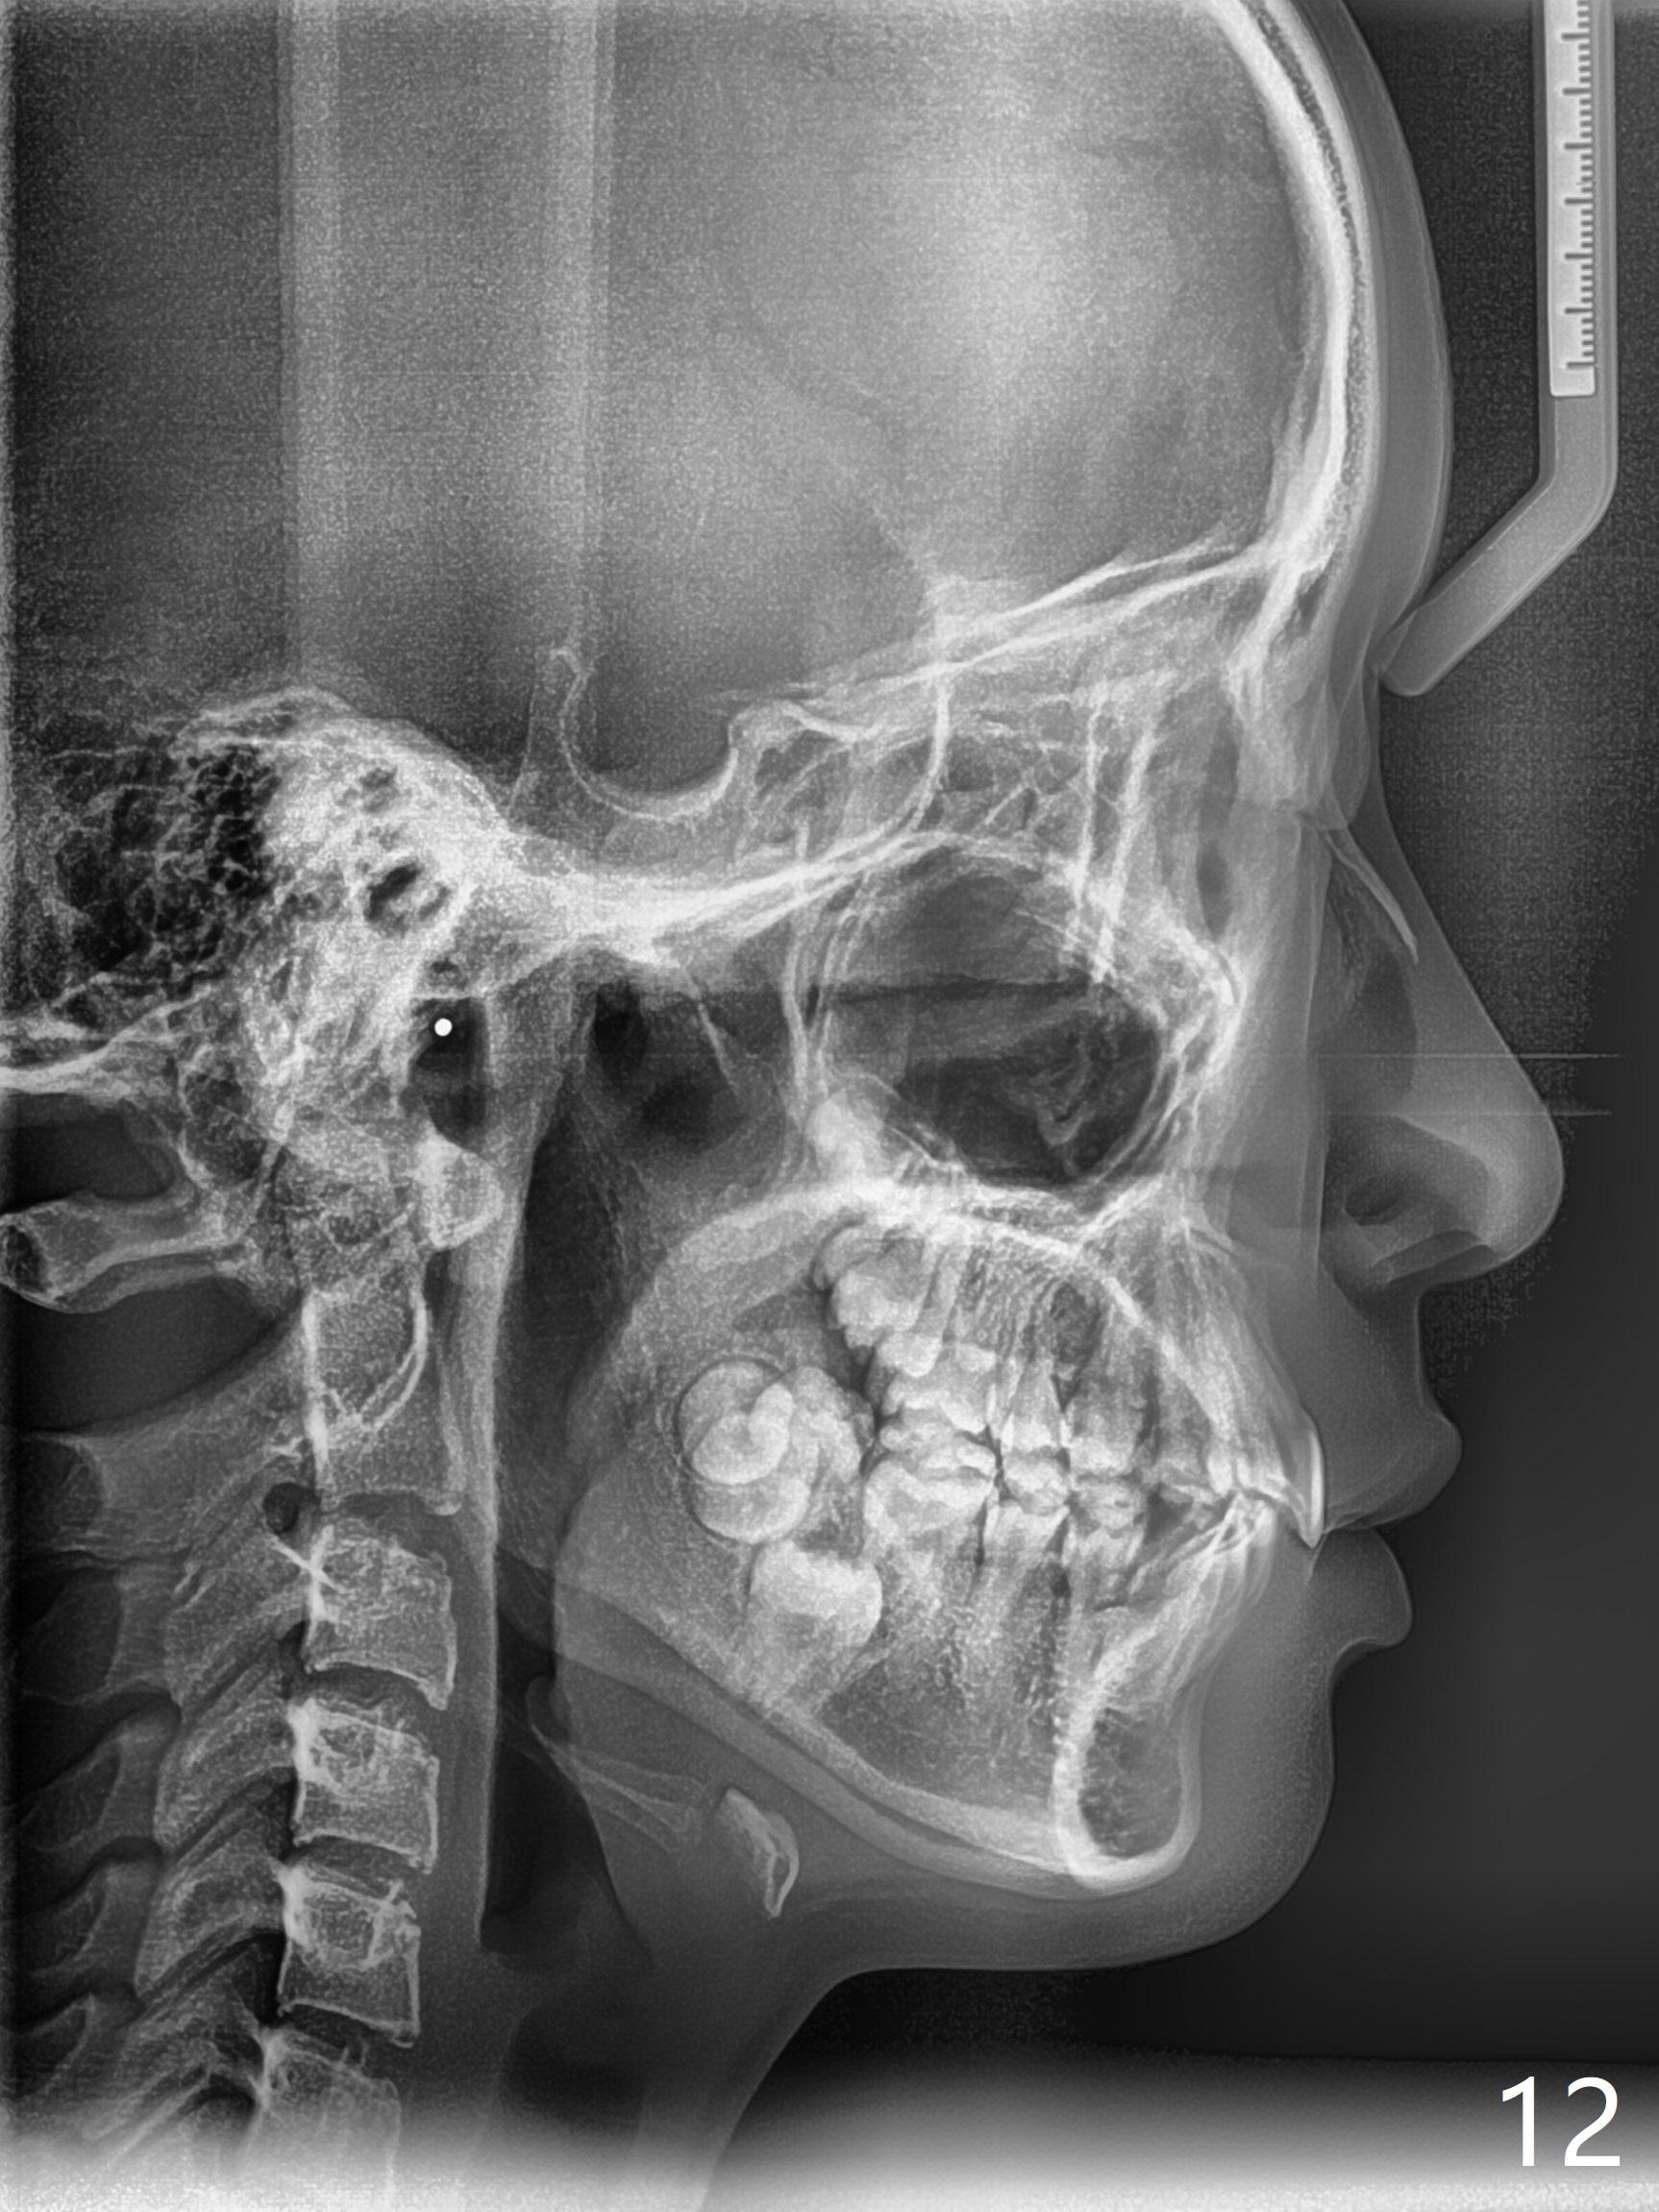

Facial Class I Occlusal Class II

A 12-year-old woman has Class I facial profile (Fig.1-4,12,13) and apparently Class II Division I malocclusion (Fig.6-11). Start Class II retraction as early as possible to take advantage of the upper and lower posterior diastemata (Fig.9,11 (in fact there is no diastema)). LL7 impaction is noted immediately prebanding (Fig.14). Surgical access is pending.